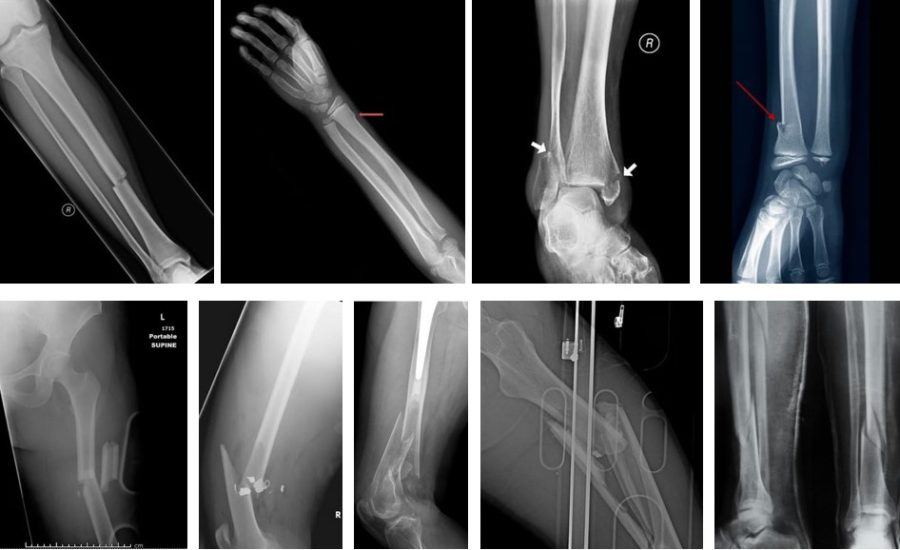

У даному матеріалі ми хочемо зробити невеликий огляд сучасних накісткових та внутрішньокісткових імплантатів – пластин та стержнів, які використовуються при фіксації переломів довгих трубчастих кісток кінцівок, як то: плечової кістки, кісток передпліччя, стегна